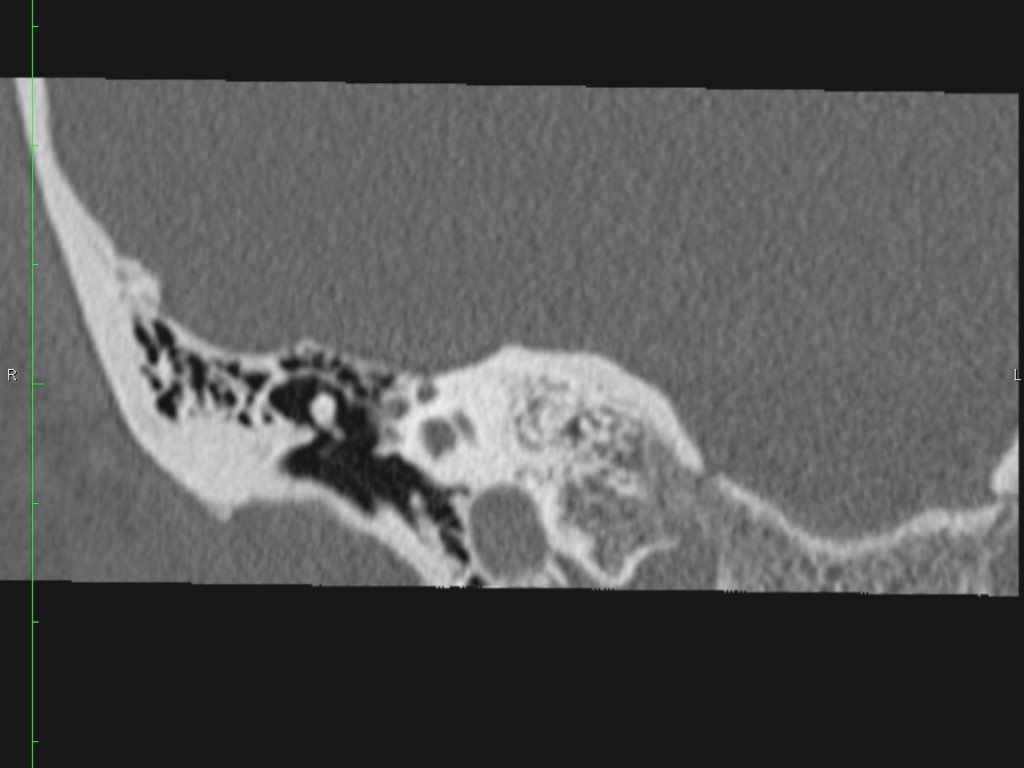

Có một khối mô mềm ở vùng thượng nhĩ.

Lưu ý hình ảnh thủng màng nhĩ (mũi tên vàng) và bào mòn ống bán khuyên ngoài (mũi tên đỏ).

Scutum bị tù mòn.

Đây thường là cấu trúc xương đầu tiên bị bào mòn do cholesteatoma, hình thành bởi sự co kéo vào trong của pars flaccida màng nhĩ vào vùng thượng nhĩ.

Nếu quá trình co kéo tiếp tục tiến triển sẽ dẫn đến phá hủy chuỗi xương con.

Nếu cholesteatoma lan ra phía sau qua aditus ad antrum vào trong xương chũm, có thể gây bào mòn tegmen mastoideum làm lộ màng cứng, đồng thời bào mòn ống bán khuyên ngoài dẫn đến điếc và chóng mặt.